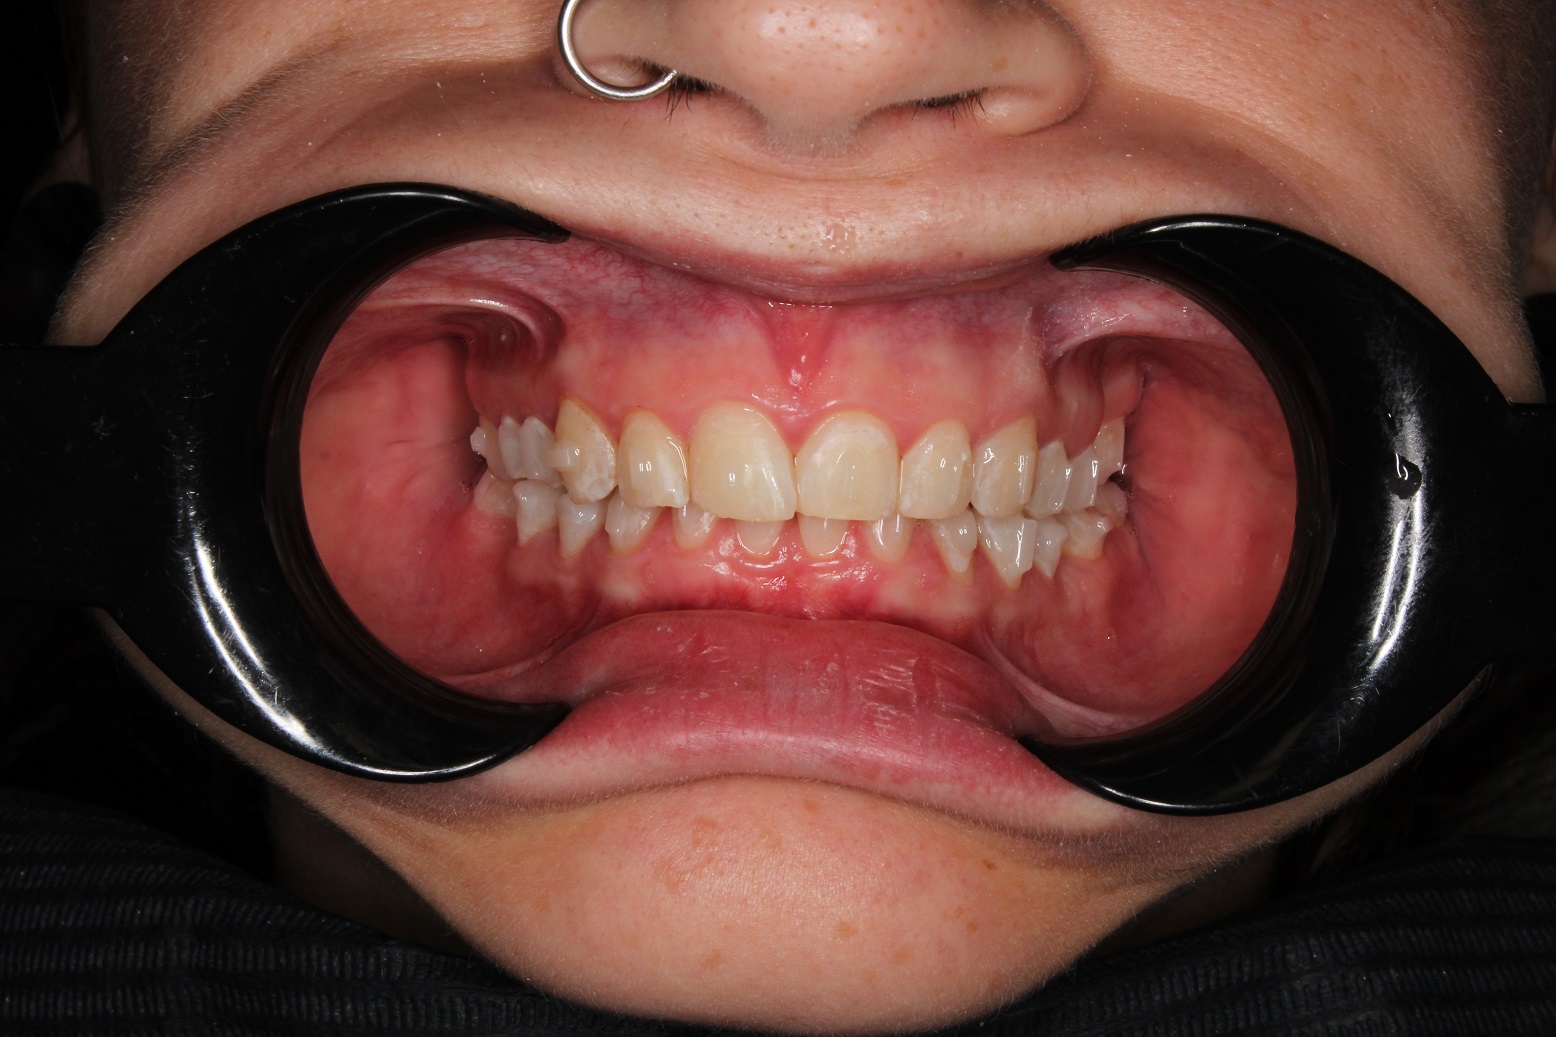

До и После: Лечение глубокого прикуса элайнерами

Лечение глубокого прикуса элайнерами. Начало лечения. Фиксация элайнеров